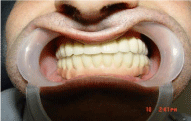

A 46 years old patient, presented to our clinic with a diagnosis of generalized periodontitis of the lower jaw, with edentulous atrophic maxilla. A comprehensive clinical and radiographic evaluation revealed advanced alveolar bone resorption rendering the prognosis of all lower teeth unfavorable. After the preliminary clinicalradiation examination, a treatment plan was defined that included the removal of all the teeth of the mandible and the installation of 8 dental implants in lower jaw, the installation of 1 dental implants in the tuber regions of the upper jawbone on both sides, the installation of 2 dental implants in zygomatic bone from both sides and installation 4 dental implants in the area of 13,14,23,24 distant teeth. 4 months after implant placement prosthetic restoration was fabricated and adjusted. The patient has been followed up for 5 years. So far, no further problem has occurred and the restoration has remained functional (Figures1-8).

Figure 6: Clinical appearance after prosthetic rehabilitation with non-removable metal-ceramic prosthetic restoration

Figure 7: Clinical appearance after prosthetic rehabilitation with non-removable metal-ceramic prosthetic restoration